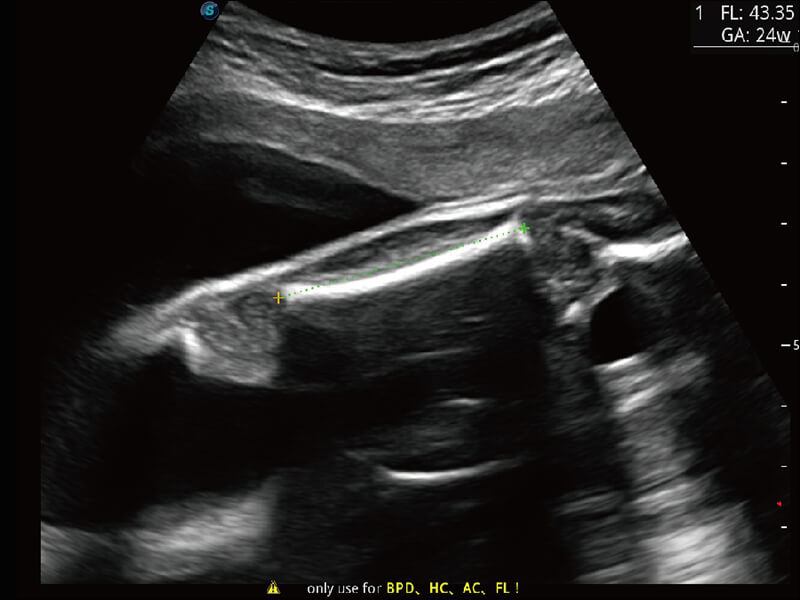

性能优异的硬件架构,极大提升超声系统的运行效率和数据处理能力。相比以往超声成像系统,Wis+平台为您带来极快的响应速度和成像帧频,提升检查流畅度。